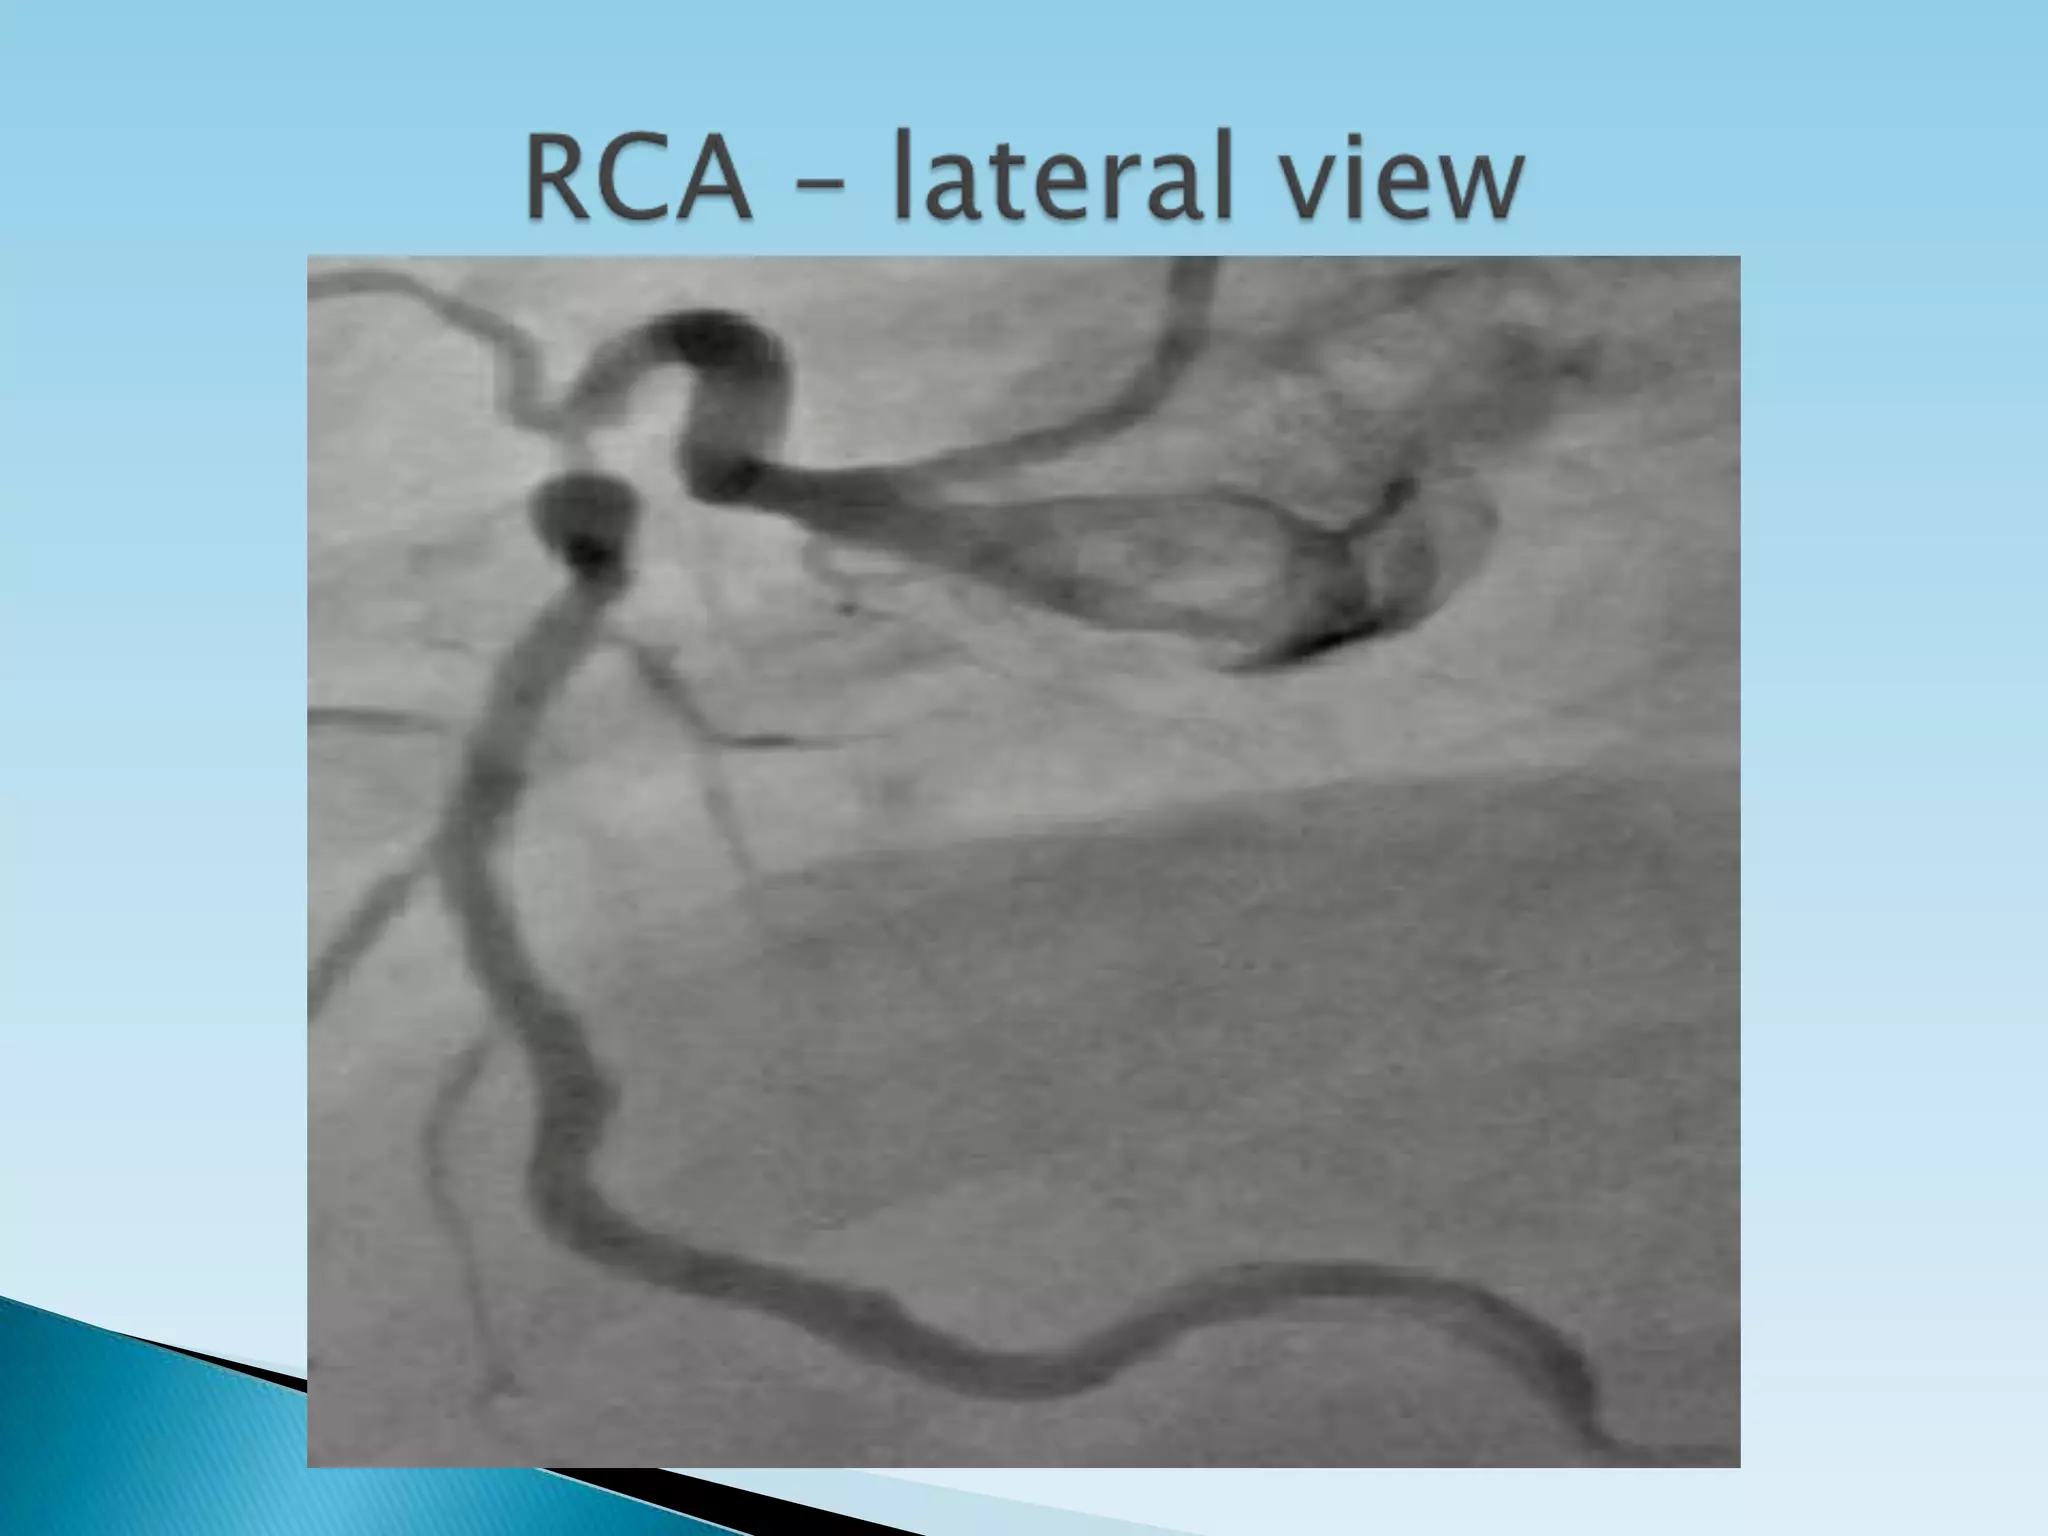

Proximal RCA          LAO, Lateral

Mid RCA               LAO, Lateral, RAO

RCA arises from the right coronary cusp and follows the right AV groove.  The most proximal branches of the RCA are the conus-branch which supplies the Right ventricular outflow tract and a branch that supplies the sino-atrial (SA) node (60% of patients).  RCA gives off the postero lateral and posterior descending branches at the crux cordis

Anatomic landmarks formed by the spine, catheter and diaphragm provide information to discern which tomographic view from which the image is obtained.  In the LAO view the catheter and spine are seen on the right side of the image, while in the RAO they are found on the right.  PA imaging places these landmarks in the center.  Cranial can usually be distinguished from caudal angulation by the presence of the diaphragm. For cranial imaging, the patient should be asked to inspire to remove the diaphragmatic shadow from the image.

Proximal circumflex RAO cranial, LAO caudal Intermediate RAO caudal,LAO caudal Obtuse marginal RAO caudal, LAO caudal, RAO cranial Proximal RCA LAO, Lateral Mid RCA LAO, Lateral, RAO Distal RCA LAO cranial, Lateral PDA LAO cranial Posterolateral LAO cranial, RAO cranial